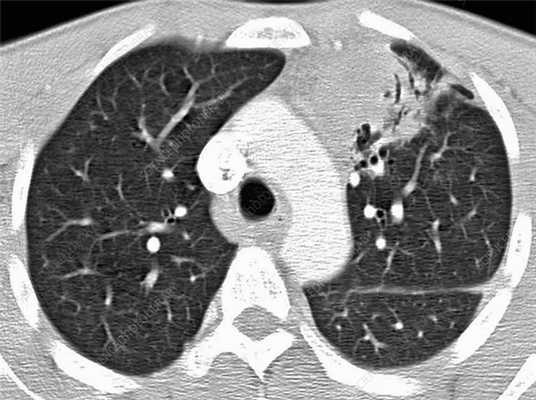

Лимфома легких на КТ

Признаки лимфомы легких особенно выражены на четвертой стадии заболевания, когда болезнь поражает дыхательный орган. На КТ при этом будут видны увеличенные лимфоузлы, формирующие цепочки, конгломераты. При этом у пациента может также наблюдаться отек легких. Однако высокая разрешающая способность КТ позволяет выявить лимфому на ранней, первой стадии.

На КТ лимфомы, как и любые уплотнения, визуализируются сравнительно более светлым цветом. В норме воздушная легочная паренхима практически однородного темного цвета. Иногда таких уплотнений несколько и они диссеминированны. Контуры лимфомы четкие и ровные. Вокруг патологических очагов обнаруживаются участки «матового стекла».